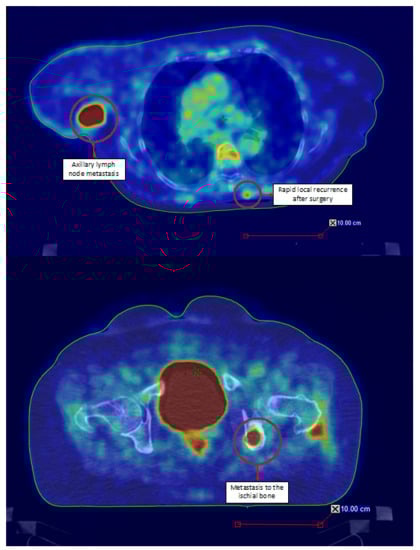

- Sachpekidis, C.; Sidiropoulou, P.; Hassel, J.C.; Drakoulis, N.; Dimitrakopoulou-Strauss, A. Positron Emission Tomography in Merkel Cell Carcinoma. Cancers 2020, 12, 2897. [Google Scholar] [CrossRef]